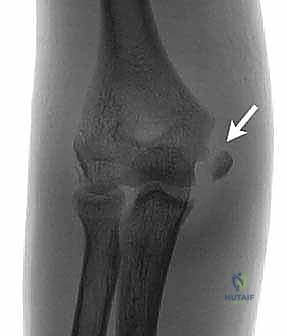

- التصوير بالأشعة السينية (X-rays): يتم أخذ صور من زوايا متعددة (أمامية خلفية AP، وجانبية Lateral، ومائلة Oblique). في حالة الأطفال، قد يطلب الدكتور هطيف صورة للمرفق السليم للمقارنة، نظراً لتعقيد مراكز النمو العظمي (Ossification centers) في هذا العمر.

- الأشعة المقطعية (CT Scan): في الكسور المعقدة أو المفتتة، أو عند الاشتباه بوجود قطعة عظمية محشورة داخل المفصل، يتم اللجوء للأشعة المقطعية للحصول على صورة ثلاثية الأبعاد تساعد في التخطيط الجراحي الدقيق.

- القطعة المحشورة (Incarcerated Fragment): إذا دخلت القطعة المكسورة داخل المفصل ومنعت حركته (وهي حالة طارئة).